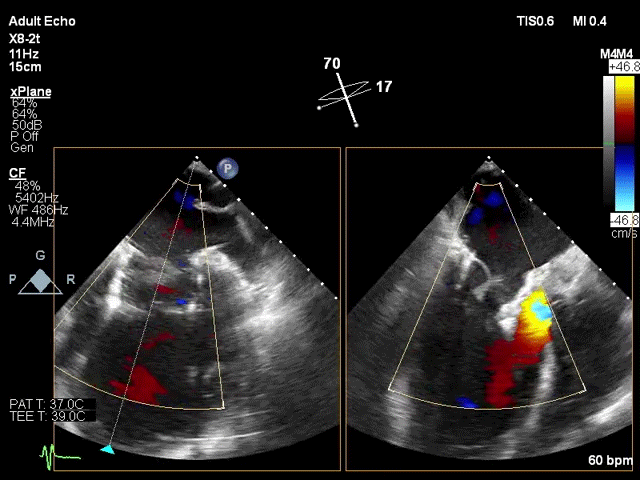

该手术采用左侧第五肋间微创切口心尖入路,透视下经导丝置入输送系统,逐步释放瓣膜。透视及TEE确认瓣膜位置满意后撤出输送系统,二尖瓣瓣膜形态及工作状态良好,复查左心室造影,提示无瓣周漏,无左室流出道梗阻,左右冠状动脉显示良好,未受任何影响。

心电图提示无传导阻滞,左房压由术前52/32/18mmHg降至25/21/18mmHg 。